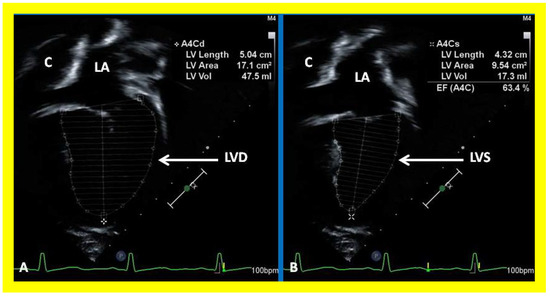

Subsequent to completion of Fontan procedure, periodic clinical follow up along with echo-Doppler studies is generally recommended at 1, 6, and 12 months after the procedure and yearly thereafter [36,37,38]. The LV is usually normal in size with normal LV systolic function (Figure 38) because the pulmonary and systemic circulations are completely separated during the final phase of Fontan. However, some patients may have dilatation of the LV with or without diminished LV systolic function, secondary to prolonged exposure to volume overloading, significant mitral insufficiency, previously undetected myocardial damage due to multiple surgical procedures under cardio–pulmonary bypass, or a combination thereof.

Figure 38. Selected video frames showing left ventricle (LV) in diastole (LVD) (A) and in systole (LVS) (B) demonstrating normal ejection fraction (EF) of 63.4%. C, conduit; LA, left atrium.